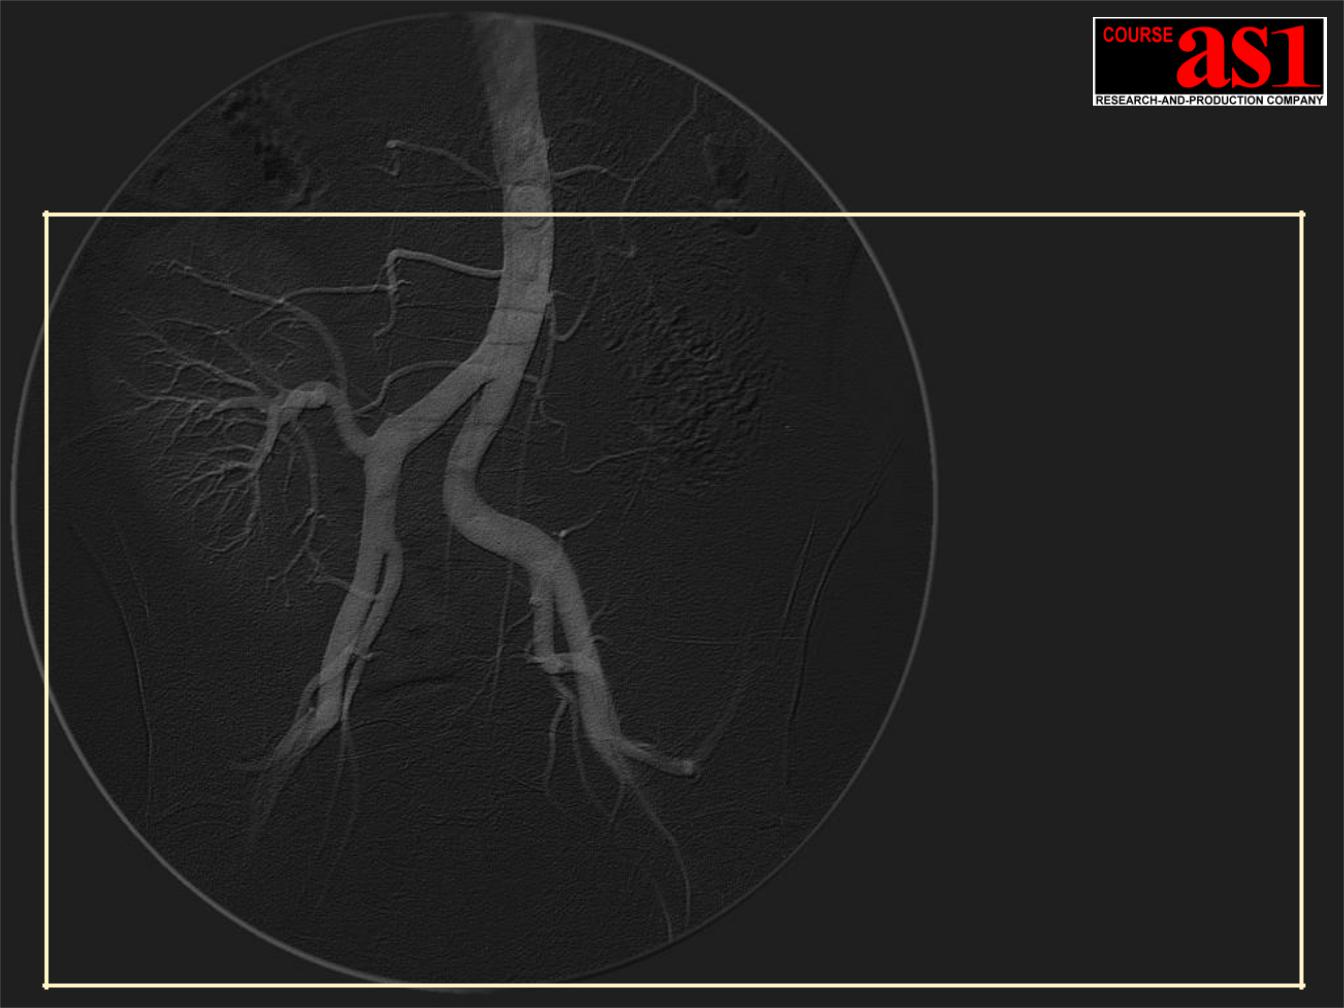

4. Режим Субтракционной Ангиографии Реального Времени – Subtraction Angiography (DSA) сверхвысокого разрешения 9Mpix/30fps или 2Mpix/60fps.

5. Режим Ротационной Ангиографии Rotational Angiography (RA) сверхвысокого разрешения 9Mpix at 30fps, включая DSA режим.